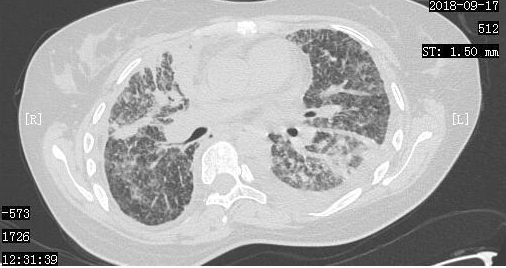

在经历了短暂的绝望后,小周一家决定齐心协力,积极进行抗癌治疗。2018年9月7日,小周进行了胸腔穿刺抽液,同时进行了胸腔灌注化疗。2018年9月14日,小周来到了我们医院进行治疗,复查了胸部CT,当时的胸部CT显示肺部一般情况非常差。

2018-9-17日CT